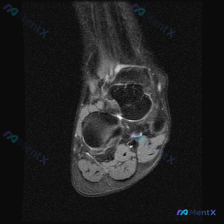

目前核心信息是:临床怀疑足踝部存在软组织积液,提供了一张足踝部冠状位T2加权(脂肪抑制)MRI图像,要求读片判断,推测患者伴随足踝部疼痛或不适症状。

- 图像基本情况:标准冠状位T2加权脂肪抑制序列,扫描层面位于踝关节后方至距下关节区域,解剖结构清晰,信噪比可,无明显运动伪影。

- 骨骼信号与结构:距骨、跟骨骨髓信号正常,轮廓完整,皮质连续,未见骨髓水肿、骨折线、骨质破坏或骨赘形成。

- 关节与软组织:距下关节间隙清晰,对位正常;所有主要肌腱信号规则、边界清晰走形连续,无肌腱内高信号或增粗;皮下脂肪层信号均匀,距下关节间隙及周围软组织间隙内未见异常高信号液体积聚,也没有软组织肿块或异常结节。

- 读片总结:这一特定切面上,未见明显解剖异常或病理性信号改变,没有找到临床怀疑的「软组织积液」。